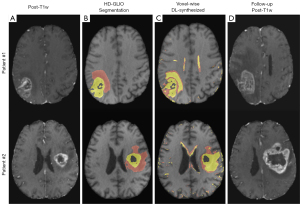

Table 1 shows the sensitivity and specificity obtained for each classification (i.e., C-I and C-II defined in section “Classification method 2: voxel-wise statistical prediction from pre-contrast maps”) for both MAGiC and synthesized maps. As can be seen in that table, synthesized maps obtained similar performance compared to MAGiC for discriminating normal from ABN (C-I) with sensitivities: 88.37% (IQR, 17.30%) vs. 89.35% (IQR, 8.93%) and slightly better discriminating tissue with and without T1e (C-II) with sensitivities: 93.26% (IQR, 14.05%) vs. 87.29% (IQR, 16.62%) and P=0.0015. Also for both maps, the segmented T1e and T2h regions obtained through the statistical prediction from both MAGiC and synthesized maps are shown in Figure 4 for a representative test patient. The segmentations obtained with HD-GLIO from weighted images are also shown as reference. An extended version of Figure 4 with all the GLIOMA patients was provided in Figure S3.

Figure 6 shows a comparison between the segmentation obtained with the voxel-wise statistical prediction from DL-synthesized maps and the reference HD-GLIO segmentation for UPenn-GBM. Sensitivities and specificities for the voxel-wise prediction with the synthesized maps are shown in Table 2. The metrics reported are sensitivities of 91.23% (IQR, 10.14%) and 81.04% (IQR, 24.21%) and specificities of 90.24% (IQR, 3.55%) and 91.49% (IQR, 6.14%) for C-I and C-II, respectively. These values are comparable to those reported in Table 1 for GLIOMA.

Interestingly, the statistical prediction shows a slight overestimation of the T1e region compared to HD-GLIO, but there is also some coincidence with the follow-up images shown in Figure 6. This region presents T1 and T2 values higher than those of the nWM, resulting in the region being classified as T1e. Nevertheless, we hypothesize that these higher values could be explained by an altered interstitial fluid mobility and increased water content in the perivascular space (34), even when the BBB is not completely disrupted for GBCA to pass through. Thus, this overestimated T1e region could represent a BBB vulnerability and, therefore, it might be an appropriate follow-up biomarker. This hypothesis agrees both with recently reported findings (8,35) and, apparently, with our results on the UPenn-GBM follow-up images (see Figure 6). However, further research is necessary to confirm this hypothesis.